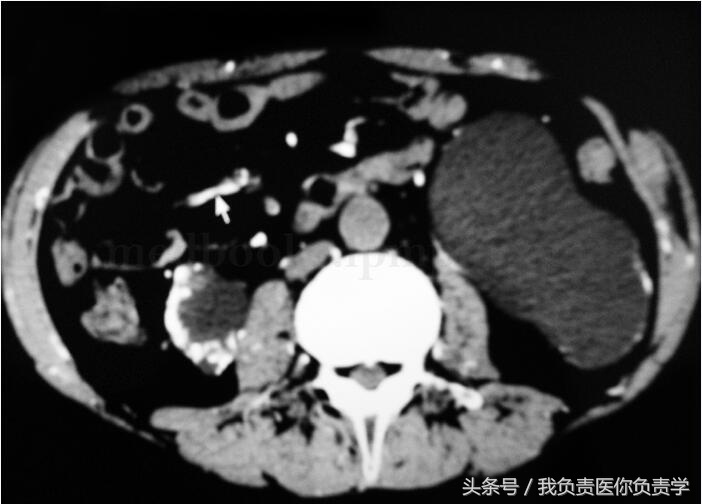

其他检查:左右足正斜位片:检查所见构成双足各骨骨质疏松,未见明确骨质增生及破坏,未见骨折,双足各关节未见异常。印象诊断双足骨质疏松。胸片(图35‐5):心、肺、膈未见异常。胸部CT:检查所见两肺透亮度减低,呈毛玻璃样改变,以双上肺明显,右下肺后基底段可见钙化点,余两肺未见结节及片状病灶,气管及叶、段支气管无狭窄,肺门、纵隔未见明确肿大淋巴结。心脏无扩大,胸膜无结节,胸腔无积液,胸壁未见确切异常。印象诊断:双肺呈毛玻璃样改变,考虑慢性肾衰竭引起心肺改变。泌尿系彩超:左肾区不纯液性包块;右下腹移植肾血流显示较稀少。下腹部CT:检查所见左侧髂窝可见移植肾,其形态、大小未见异常改变,移植肾内侧可见扩张的输尿管,前列腺形态、大小正常,内见散在钙化斑,膀胱充盈不佳,膀胱精囊角存在,直肠结构未见异常,盆壁未见肿大淋巴结,盆腔、双侧腹股沟区、双侧臀部血管广泛钙化。印象诊断:左侧髂窝移植肾形态、大小未见异常改变,左侧输尿管扩张积水;盆腔、双侧腹股沟区、双侧臀部血管广泛钙化。腹部CT(图35‐6):双肾皮质变薄,并见大量蛋壳样钙化,双肾盂、肾盏及左侧输尿管上段扩张积水;移植肾大小、位置、形态未见明显异常;腹部血管广泛钙化;胆囊结石。心电图(图35‐7):窦性心律,大致正常心电图。

图35‐7 腹腔CT 平扫:双肾大量蛋壳样钙化;腹部血管广泛钙化